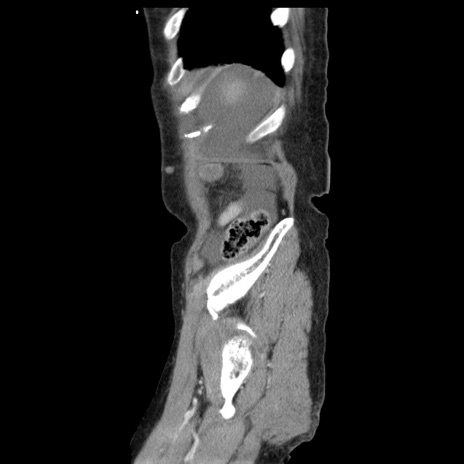

症例1(矢状断像)

【症例】80歳代女性

【主訴】腹痛

【現病歴】8時間前から腹痛あり来院。

【既往歴】糖尿病、脂質異常症、子宮体癌にて子宮全摘術

【身体所見】意識清明・会話良好だが腹痛で苦悶様、全腹部にわたって反跳痛と圧痛あり

【データ】WBC 13600、CRP 0.14、LDH 224、CK 90